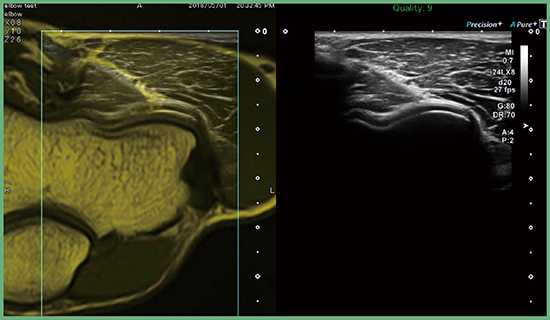

Aplio iシリーズに搭載できる“Smart Fusion”は,プローブに装着されたポジションセンサにより位置情報をリアルタイムに認識し,あらかじめ装置内に保存したMRIやCTのボリュームデータから超音波断層像に対応するMRIやCTの断層像を切り出し,超音波画像と並べて表示あるいは重畳表示することができる。図7は,肘のMRIと超音波画像の重畳画像である。MR画像をガイドにすることにより,超音波断層像が理解しやすくなることが期待される。

図7 重畳画像と超音波断層像の並列表示